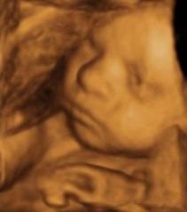

L’adattamento all’ambiente extrauterino è uno dei compiti principali che il bambino si trova ad affrontare alla nascita e durante i primi mesi di vita. ...